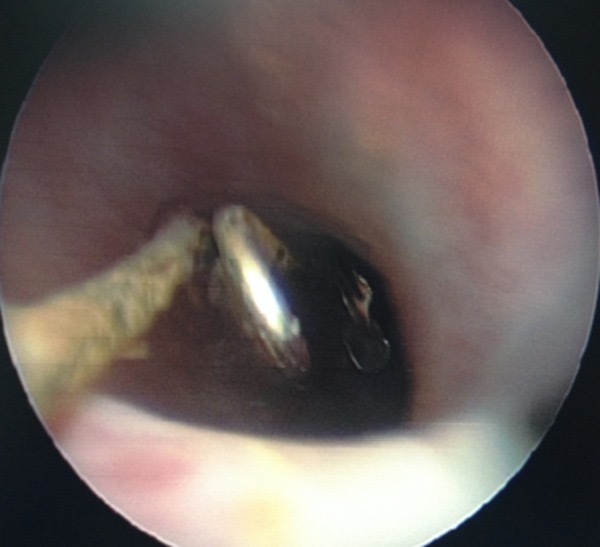

Английская булавка была удалена под контролем уретроцистоскопа.

Figure 5. Уретроскопическое удаление металлического инородного тела.